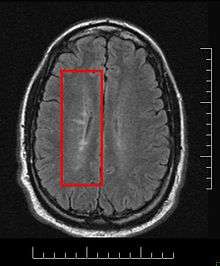

Normally MS lesions are small ovoid lesions, less than 2 cm. long, oriented perpendicular to the long axis of the brain's ventricles [18] Often they are disposed surrounding a vein[19]

Active and pre-active lesions appear as hyperintense areas under T2-weighted MRI. Pre-active lesion here refers to lesions localized in the normal appearing white matter, without apparent loss of myelin but nevertheless showing a variable degree of oedema, small clusters of microglial cells with enhanced major histocompatibility complex class II antigen, CD45 and CD68 antigen expression and a variable number of perivascular lymphocytes around small blood vessels[20]

Recently, it has been remarked that it can plausibly be accounted for by veno-venous reflux,[31][32] according to the CCSVI theory. This results in a finger-like appearance of the lesions extending mainly off the ventricles within the brain.

This morphologic appearance was named Dawson's fingers by Charles Lumsden, after the Scottish pathologist James Walker Dawson,[33] who first defined the condition in 1916.

Dawson's fingers

"Dawson's fingers" is the name for the lesions around the ventricle-based brain veins[34][35] of patients with multiple sclerosis. The condition is thought to be the result of inflammation or mechanical damage by blood pressure[30] around long axis of medular veins.

Dawson's fingers spread along, and from, large periventricular collecting veins, and are attributed to perivenular inflammation.[36]

Lesions far away from these veins are known as Steiner's splashes.[30]